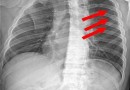

늑골 골절

늑골 골절 (정의)흉곽 골절은 일반적으로 낙상, 차량 사고, 또는 야구 방망이에 맞는 것과 같은 강한 둔탁한 힘이 가해져 발생합니다. 그러나 때로는 골다공증이 있는 고령자의 경우에는 약간의 힘(경미한 넘어짐 등)만 가해도 골절이 발생합니다.골절 자체는 심각한 경우가…